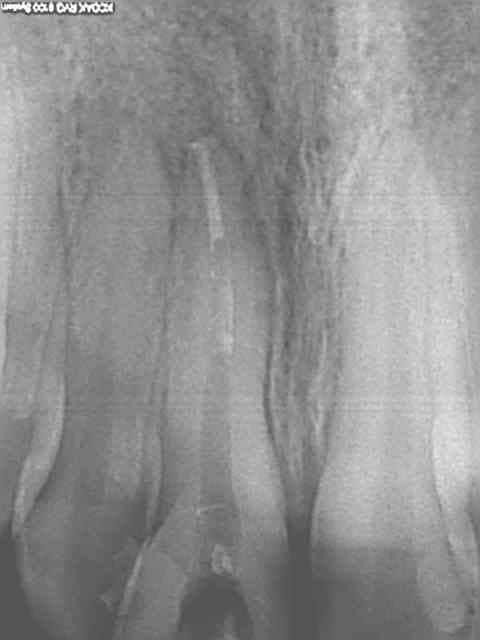

Radio initiale, cone en place , cone scellé, radio du bouchon apical réalisé au système b, puis radio finale après thermo-condensation. C'est obligatoire avec la nouvelle CCAM. Fini de jouer au dentiste le 1er juin.)))))))

Elles sont dans le désordre , remets les en ordre ( ca fait partie d'un qcm de formation continue) vu que le niveau de la formation initiale semble resté bloqué dans les années 80.